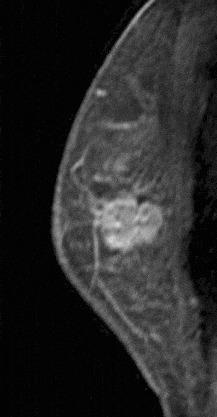

Internal enhancement of masses can be described as homogeneous or heterogeneous. Homogeneous enhancement is confluent and uniform (Fig. 8). Heterogeneous enhancement is non-uniform with areas of variable signal intensity (SI) (Fig. 9). Heterogeneous enhancement can be further classified as rim (Fig. 10), dark internal septations (Fig. 11), enhancing internal septations (Fig. 12) or central enhancement (Fig. 13).

Figure 9. Heterogeneously enhancing mass. Pathology – Infiltrating ductal carcinoma.